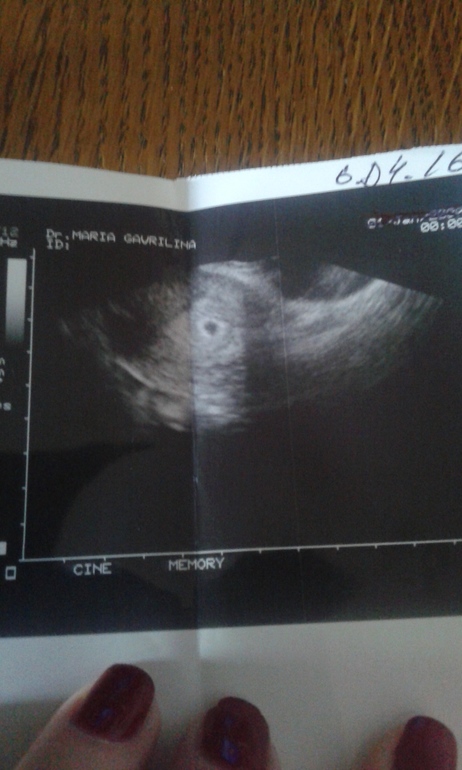

Здравствуйте,позлравляю Вас от всей души... Извините а Вы не скажете размер плодного яйца?Просто тут срок Б почти как у меня 3 нед от зачатия т.е 5 нед бер.Пожалуйста если не трудно,а то у меня одна паника(( Еше раз Вас поздравляю.

А мне врач не сказала.вот в четверг пойду и уже всё скажут

Спасибо.Просто всего боюсь..Но верю в лучшее.Уже сделали 3 узи и все у них под вопросом,рано я слишком пошла,через неделю опять на узи ,я не пойду подожду до 7-8 нед акушерских 5-6 нед от зачатия,думаю там уже будет все ясно и понятно,а то это только одни нервы.. Как раз и на учет встану))Вы во скольуо планируете встать?))

Ох.ещё 2 недели ждать до след узи.и можно услышать туктуктук.

Спасибо.но ещё долгие 2 недели до узи.